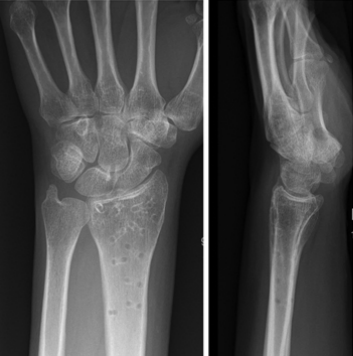

桡骨远端骨折:从解剖到手术的全面阐述

桡骨远端骨折:从解剖到手术的全面阐述...